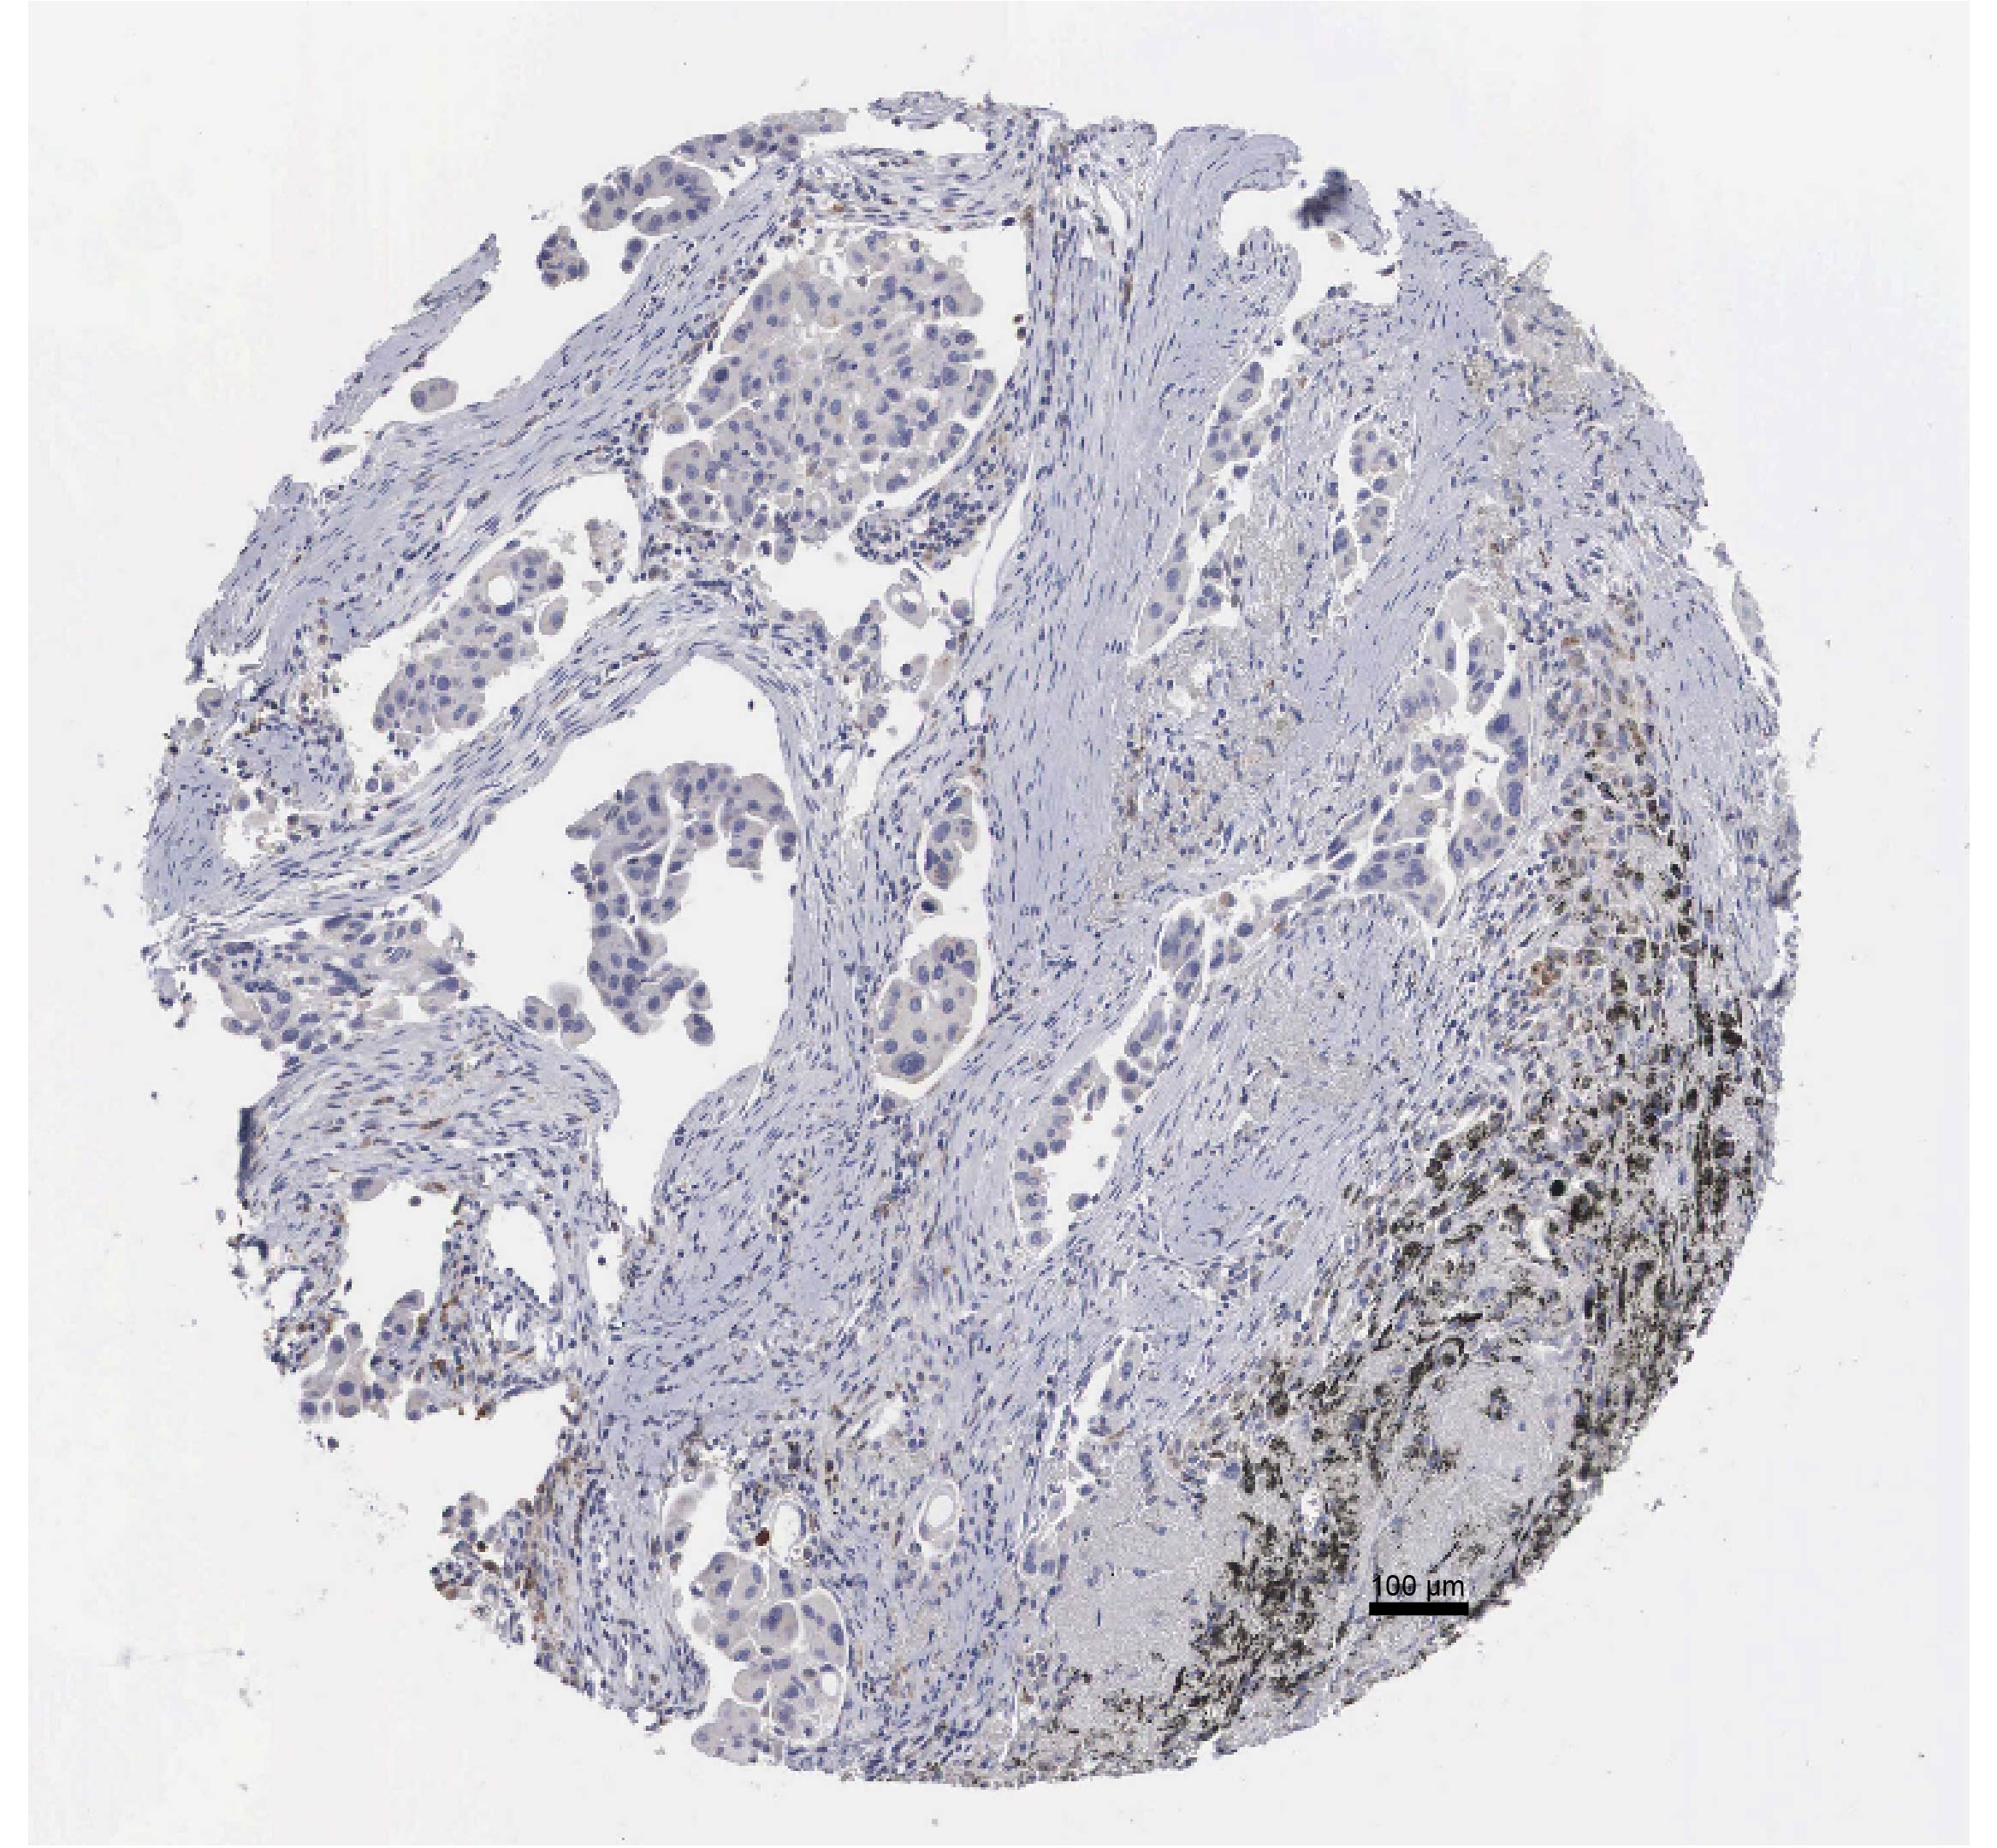

Validation of the potential biomarkers by in vitro experiments

To verify the expression profiles of P2RY13, CYTIP, ZYX, KLRB1, and HMOX1 across different cell types, we first performed quantitative experiments in BEAS-2B cells (a control cell line), A549 and H2228 cells (two lung cancer cells). It was found that the relative mRNA expression levels of P2RY13, ZYX, and KLRB1 were significantly higher in BEAS-2B cells compared to A549 and H2228 cells (Figure 6A, p<0.01). In contrast, the expressions of CYTIP and HMOX1 were markedly upregulated in A549 and H2228 cancer cells (Figure 6A, p<0.01), with HMOX1 showing a particularly high expression in A549 and H2228 cells. Hence, HMOX1 was further analyzed in subsequent experiments. We obtained immunohistochemical staining results of HMOX1 based on HPA (Supplementary Figure S8). Wound healing assay and transwell assay were conducted to investigate the role of HMOX1 in cancer cell behaviors. The results demonstrated that silencing HMOX1 in A549 and H2228 cells significantly impaired the wound healing capacity (Figure 6B, p<0.01), which was accompanied by a notable decrease in the number of migrating and invading cells (Figure 6C, p<0.01). The finding suggested that HMOX1 promoted the migration and invasion of LUAD cells.

Figure 6:

The results of in vitro validation experiments for the five key genes. (A) Relative mRNA expressions of P2RY13, CYTIP, ZYX, KLRB1, and HMOX1 in BEAS-2B, A549, and H2228 cells. (B) The impact of HMOX1 silencing on wound healing of A549 and H2228 cells. (C) Effects of HMOX1 silencing on the invasion of A549 and H2228 cells tested via transwell assay. All the experimental data of independent triplicates were expressed as mean±standard deviation. **p<0.01, ***p<0.001, ****p<0.0001.